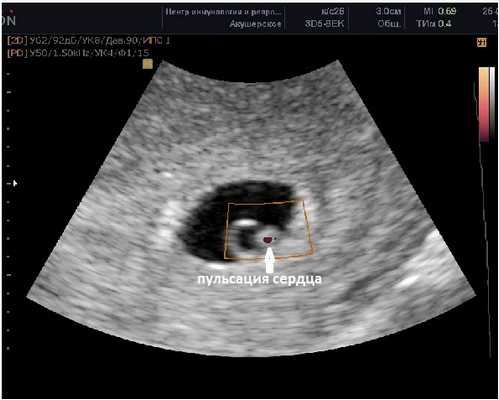

Фото УЗИ плода при беременности 6-7 недель

Внутри плодного яйца мы видим "колечко с драгоценным камнем" :) - это желточный мешок и уже хорошо различимый эмбрион, расположенные рядом. Сердце эмбриона начинает биться в начале 6-й акушерской недели беременности. Именно наличие пульсации сердца является достоверным ультразвуковым признаком прогрессирующей беременности. При КТР ≥6 мм и отсутствии пульсации сердца делается заключение об остановке развития данного эмбриона. Нормальная частота сердечных сокращений (ЧСС) эмбриона в самом начале 6-й недели 70-90 ударов в минуту, но уже к концу недели становится более 100 уд. в мин. На ранних сроках беременности большее значение имеет не ЧСС, а как таковое наличие или отсутствие сердечных сокращений. Иногда, при неразвивающейся беременности можно увидеть отражение пульсации сосудов матери внутри эмбриона и принять их за сердцебиение ребёнка. Но в этом случае частота пульсации будет идентична ЧСС матери.

Наличие одного желточного мешка, одного эмбриона и одного пульсирующего сердца в подавляющем большинстве случаев говорит об одноплодной беременности. Но в очень редких случаях это могут в последствии оказаться неразделившиеся близнецы.

СВД плодного яйца 13-23 мм. КТР эмбриона 4-9 мм.